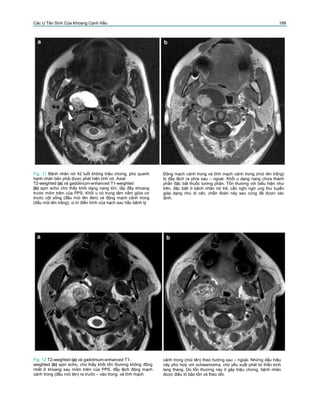

Fig. 12 T2-weighted (a) và gadolinium-enhanced T1-

weighted (b) spin echo, cho thấy khối tổn thương không đồng

nhất ở khoang sau mỏm trâm của PPS, đẩy lệch động mạch

cảnh trong (đầu mũi tên) ra trước – vào trong, và tĩnh mạch

cảnh trong (mũi tên) theo hướng sau – ngoài. Những dấu hiệu

này phù hợp với schwannoma, chủ yếu xuất phát từ thần kinh

lang thang. Do tổn thương này ít gây triệu chứng, bệnh nhân

được điều trị bảo tồn và theo dõi.

Fig. 14 Axial T2-weighted (a) và T1-weighted spino echo có

tiêm thuốc tương phản (b) ở bệnh nhân vào viện vì phù dưới

hàm. Khối tổn thương thấy ở khoang sau mỏm trâm của PPS,

gây tách rời động mạch cảnh trong (đầu mũi tên đen) và tĩnh

mạch cảnh trong (bị chèn ép, mũi tên). Tổn thương cũng đẩy

lệch nhẹ động mạch cảnh ngoài (đầu mũi tên trắng) ra trước,

nhưng trung tâm tổn thương không nằm ở chỗ chia động mạch

cảnh. Bên trong tổn thương, thấy được nhiều dòng chảy trống

giống mạch máu, cho thấy tổn thương tăng sinh mạch. Những

dấu hiệu này phù hợp với khối u glomus vagale; tổn thương

sau đó được cắt bỏ và được xác định chẩn đoán trên giải phẫu

bệnh.